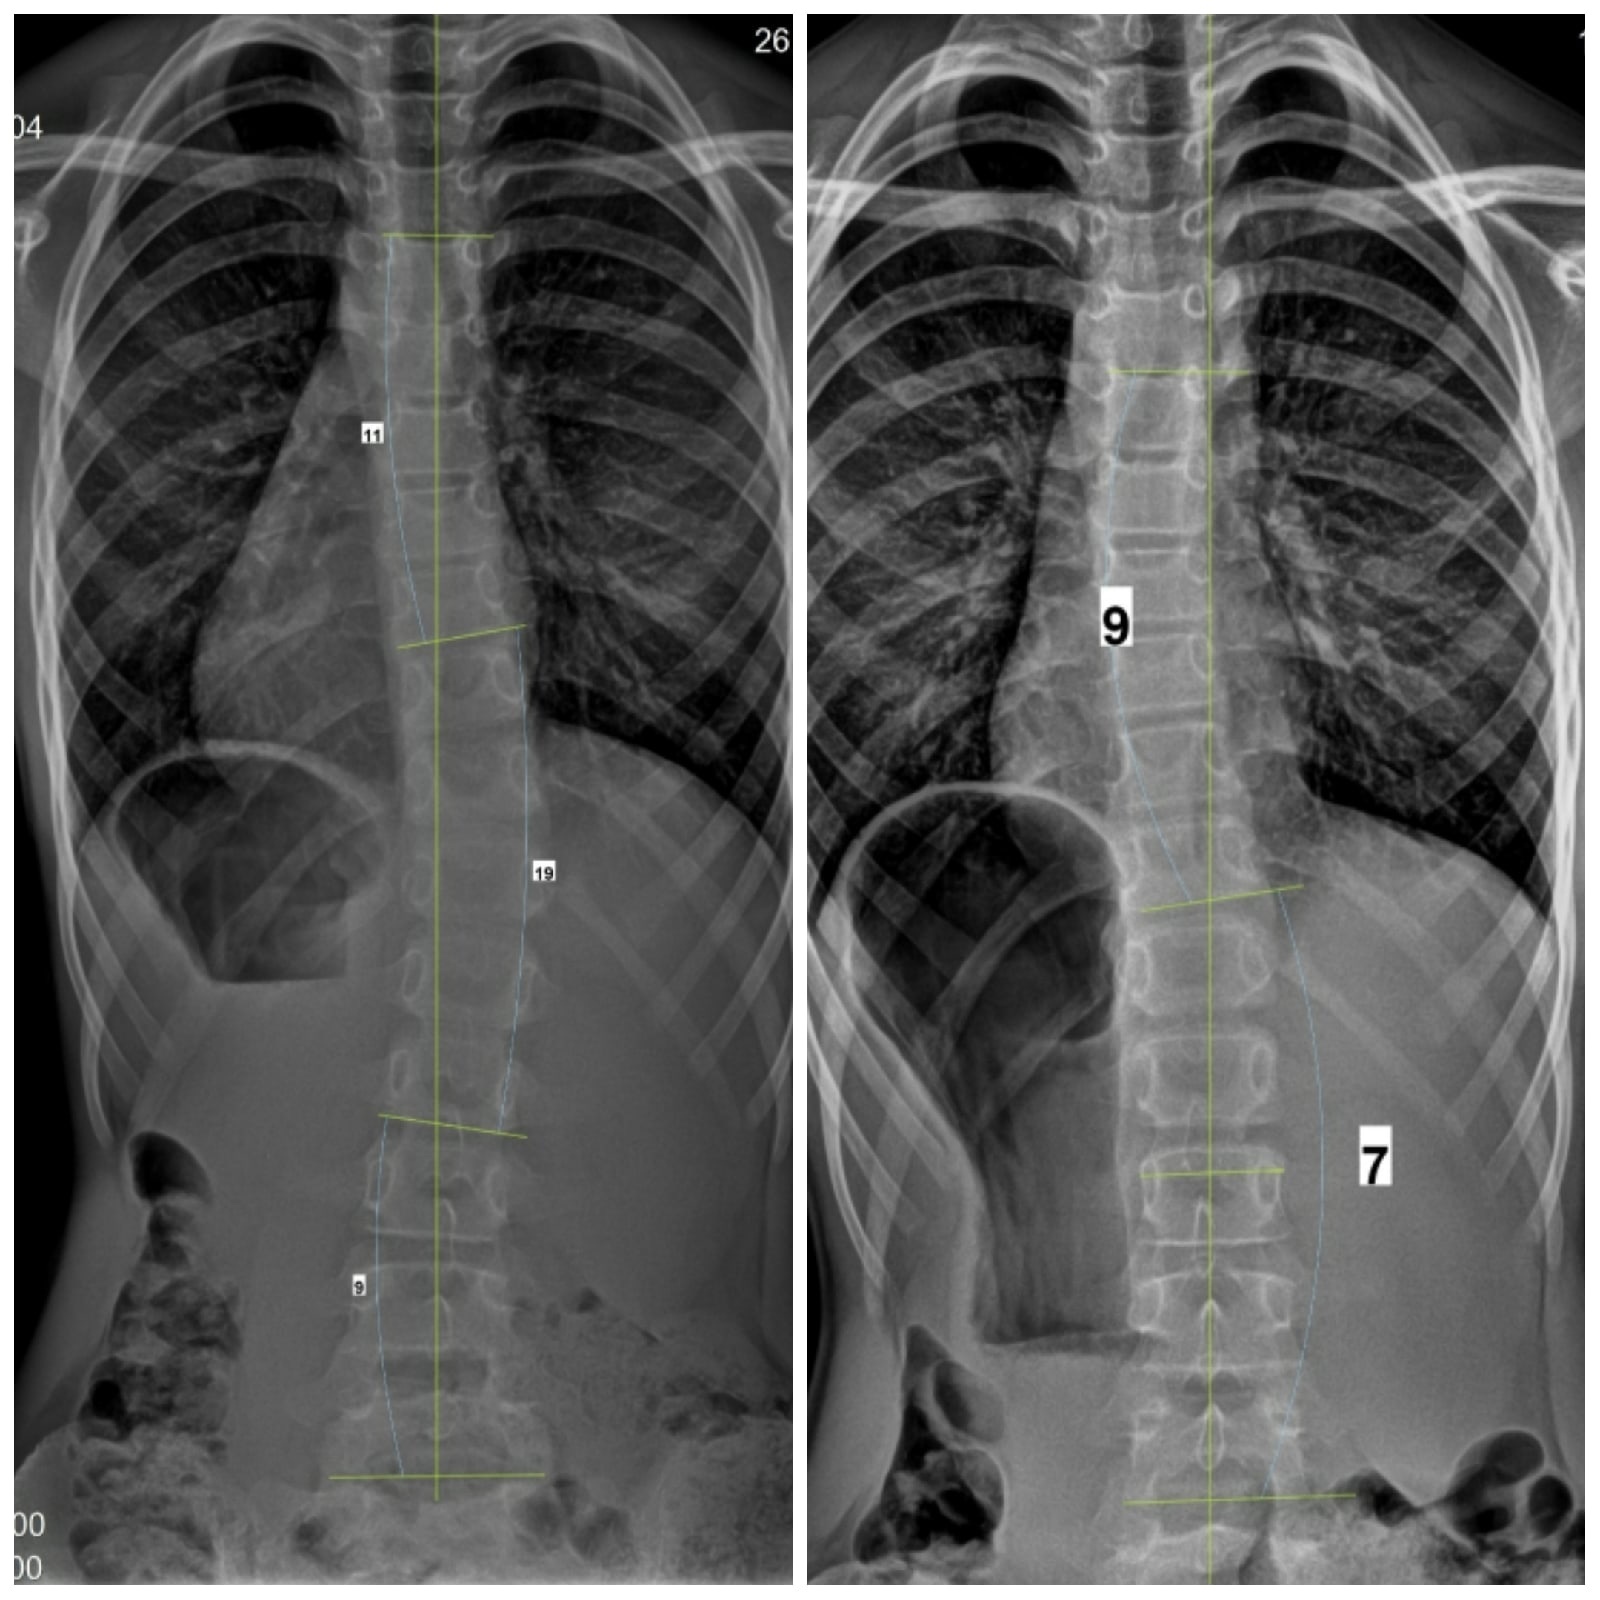

Сколиоз 19 Градусов Фото

Сколиоз 19 Градусов Фото 130 фото